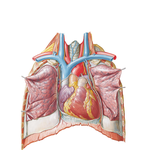

• Heart in Situ

215. Heart in Situ